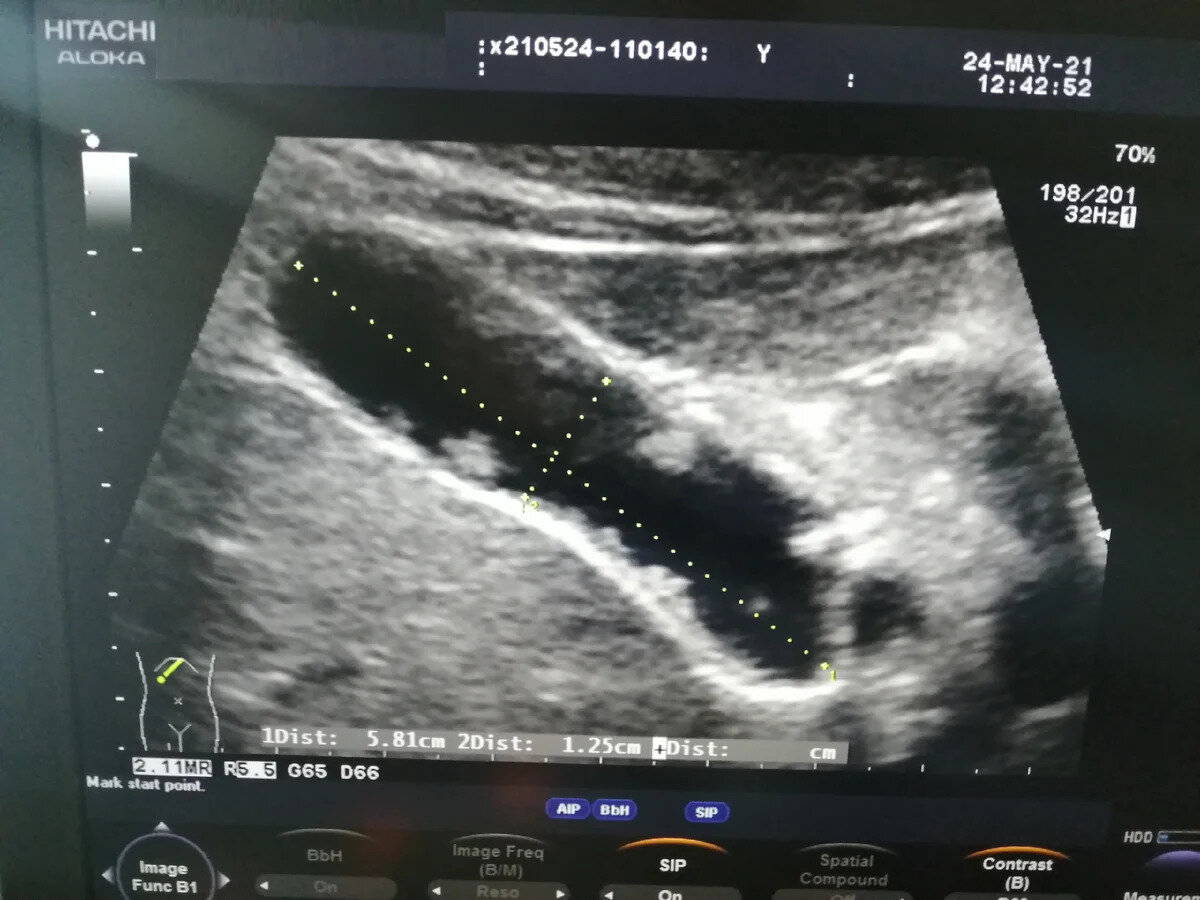

УЗИ: Перегородки в желчном пузыре и их особенности